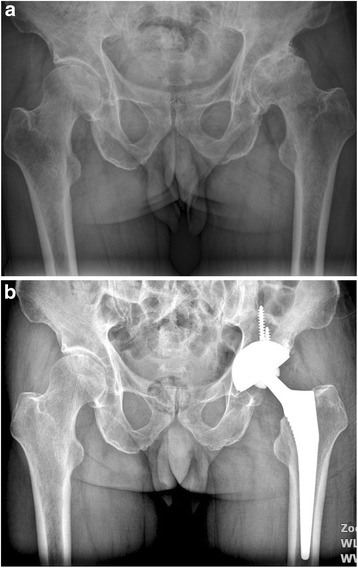

Fig. 9.

a A preoperative radiograph of the right hip of a 75-year-old man who had femoral neck fracture. b The patient had an intra-operative fracture and was treated by cerclage wire. A radiography at 42 months showed fracture healed without further complication and conventional cementless femoral stem solid fixation in a satisfactory position

Fig. 10.

a A preoperative radiograph of the hip of a 71-year-old man who had left hip osteoarthritis. b A radiograph at 44 months after implantation of conventional cementless femoral stem showed solid fixation in a satisfactory position